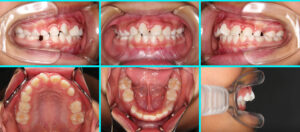

反対咬合(Ⅰ期治療の途中) 治療前 治療中 治療の詳細 主訴 上下顎右側前歯の反対咬みとそれによる歯[...] 本文を読む

Ⅰ期治療の途中